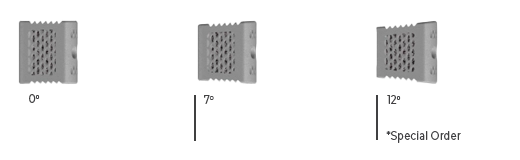

Lordosis Options